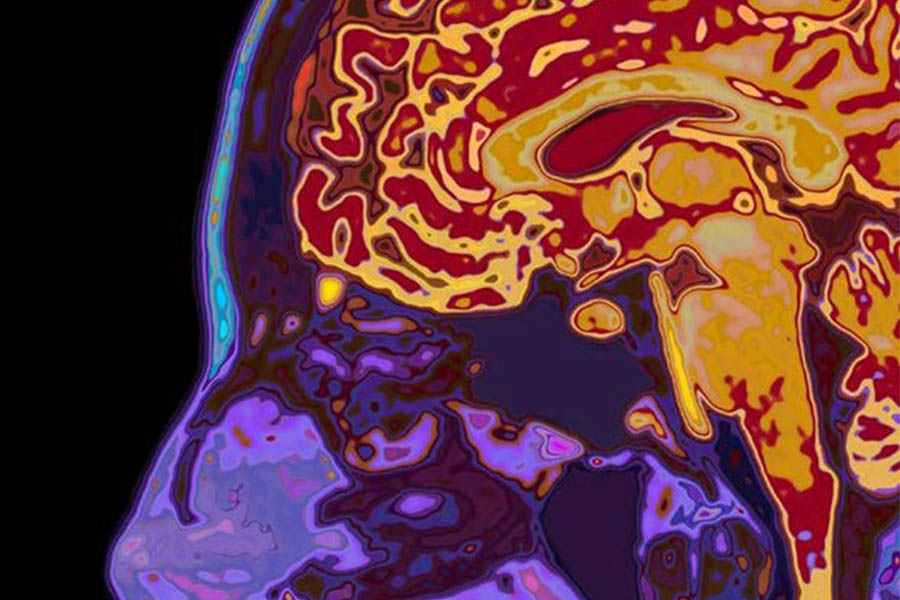

NewYork-Presbyterian/Columbia neurologists have identified brain injuries that may underlie hidden consciousness, or cognitive motor dissociation (CMD), the phenomenon by which brain-injured patients are unable to respond to verbal commands despite being able to hear and comprehend them. The team showed that brain structures related to arousal and command comprehension in CMD patients were intact, suggestive of injuries in brain circuits that relay information from the brain to muscles. This novel discovery may lead to a screening protocol for CMD using brain-imaging techniques.

CMD (green) vs. non-CMD patients’ (red) anatomical distribution of lesion patterns on structural MRI.